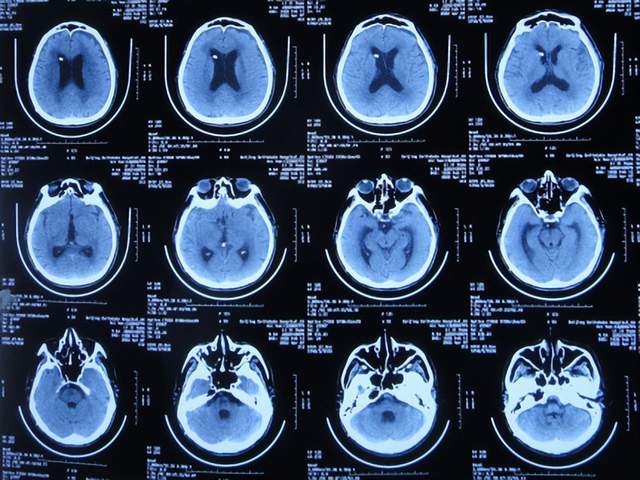

患者于2021年9月2日突发昏迷,急送至当地的山东省滨州市惠民县某医院,查头颅CT示脑出血破入脑室(图-1),急诊行双侧脑室外引流术;脑出血后血压偏低,给予输注入人血白蛋白。

图-1:2021年9月2日头颅CT

术后次日即2021年9月3日,患者意识转清醒,能简单言语,肢体可以遵嘱抬起;查头颅CT示双侧脑室引流术后,脑室积血(图-2)。

图-2:2021年9月3日头颅CT

双侧脑室外引流术后3天即2021年9月5日,查头颅CT示脑室内积血减少(图-3)。

图-3:2021年9月5日头颅CT

双侧脑室外引流术后6天即2021年9月8日,再次查头颅CT示仍有少量积血(图-4);给予常规拔除了双侧脑室外引流管,同时进行了腰大池引流术。

图-4:2021年9月8日头颅CT

腰大池引流术后4天即2021年9月12日,查头颅CT示脑室内积血基本消失(图-5)。

图-5:2021年9月12日头颅CT

拔除腰大池引流管后3天即2021年9月23日,查头颅CT示(图-6)后继续给予保守治疗。

图-6:2021年9月23日头颅CT

腰大池引流管拔除后13天即2021年10月3日,患者恢复至可以搀扶下行走约20米,能简单言语,查头颅CT较2021年9月23日认为没有明显变化(图-7)。

图-7:2021年10月3日头颅CT

但继续保留治疗20余天的时间内,患者逐渐出现意识变差,走路变差,至2021年11月3日(腰大池引流管拔除后31天),病情变重致不能走路,不能言语,查头颅CT(图-8)后考虑脑积水,给予腰椎穿刺治疗。

图-8:2021年11月3日头颅CT

但腰椎穿刺治疗7天病情无明显改善,于2021年11月10日(住院治疗2月余)出院回家休养,出院时头颅CT示仍有脑积水(图-9);出院时:意识差,不能走路,不能言语。

图-9:2021年11月10日头颅CT

出院1个半月后,因患者病情无改善,家属想做脑室腹腔分流术,于2021年12月22日前往上级的山东省滨州市某三甲医院就诊,查头颅CT示脑积水(图-10);但腰椎穿刺检查示颅内压低;胸部CT有肺部脓肿(片子丢失),暂时给予抗感染治疗。

图-10:2021年12月22日头颅CT

给予抗感染治疗个月后即2022年1月17日,肺部脓肿明显变小(片子丢失),查头颅CT仍脑积水(图-11),未给予脑室腹腔分流术,建议暂时回家休养,但患者意识仍不好,不能走路,不能说话,体型变消瘦。

图-11:2022年1月17日头颅CT

入院时查头颅CT示脑积水(图-13);肺部CT示肺部感染(图-14)。

图-13:2022年2月16日头颅CT

入院次日,给予脑室外引流术,查头颅CT示脑室外引流术后状态(图-15)。

图-15:2022年2月17日头颅CT

2022年3月1日(入院治疗13天),病情进一步改为:意识便完全正常,大小便变正常,扶着能坐起,言语交流变基本正常(图-17);头颅CT示脑室变小(图-18)。

图-18:2022年3月2日头颅CT

2022年4月7日(入院治疗50天),查头颅CT示脑室引流术后状态,未见异常(图-22)。

图-22:2022年4月7日头颅CT

2022年4月27日(入院治疗70天)家属要求出院回家休养。出院时:携带脑室腹壁外引流管;精神变得挺好,能自己站立但自己走路不稳,体重较入院时明显增加,入院时消瘦病态的体型已基本恢复正常状态(图-23);出院时头颅CT示脑室引流状态(图-24)。

图-24:出院时头颅CT

出院后4个月即2022年8月30日,为了做脑积水分流术,再次来到李小勇脑脊液科,入院时:精神状态良好,能自己走路了稍不稳(图-25);头颅CT示脑室引流术术后状态(图-26)。

图-26:2022年8月30日头颅CT

完善各项检查后于2022年9月15日,进行了脑室腹腔分流术(图-27)。

图-27:2022年9月15日头颅CT